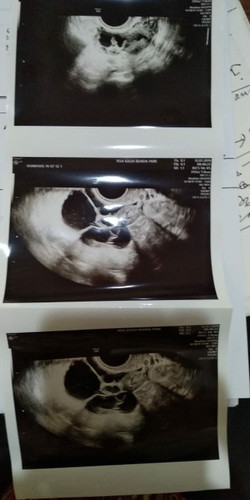

vonis dokter "hamil tanpa bayi tabung tdk akan mungkin"

Seketika hati saya langsung hancur bund. Seakan g ada lagi pandangan untuk hidup. Slama ini saya promil kmna² sudah ganti dokter bolak balik dan hasilnya slalu beda. Hari ini saya menemui dokter senior di kota tetangga, dan dari situ saya melihat langsung dgn keterangan yg jelas bahwa ada kerusakan di organ saya. Sehingga untuk mendapatkan bayi dgn cara alami sangat tdk mgkin ????? sedangkan biaya bayi tabung sangat mahal sekali. Mgkin ada yg punya pengalaman seperti saya, bisa berbagi cerita. Saya sangat butuh pencerahan dan kekuatan.